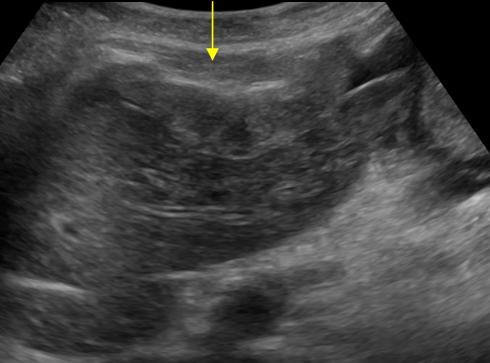

Di căn phúc mạc

Di căn phúc mạc - Ảnh 3

Di căn phúc mạc - Ảnh 4

» Thông tin: Nữ giới – 55 tuổi.

» Lâm sàng: Đau bụng / K buồng trứng.